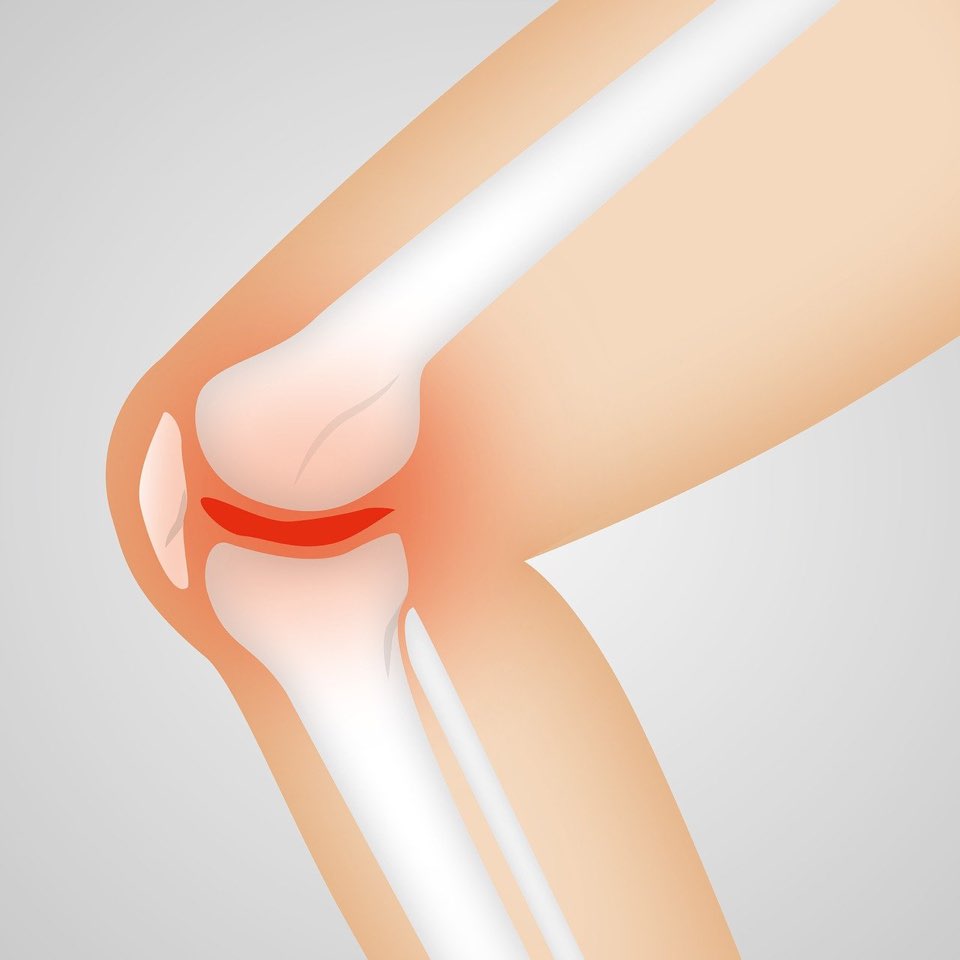

무릎 관절의 보호 연골이 부서지기 시작하면서 통증은 시작됩니다.

원래는 연골이 뼈의 끝부분을 완충시켜 부드럽고 통증 없는 움직임을 가능하게 합니다. 하지만 이 부분이 악화되면 뼈가 서로 마찰되어 통증, 염증, 뻣뻣함을 유발하여 통증을 유발하게 됩니다.

1. 글루코사민과 콘드로이틴 황산염 : 글루코사민은 연골을 만들고 복구하는 데 도움이 되며, 콘드로이틴 황산염은 연골탄력을 유지하는 데 도움이 됩니다.